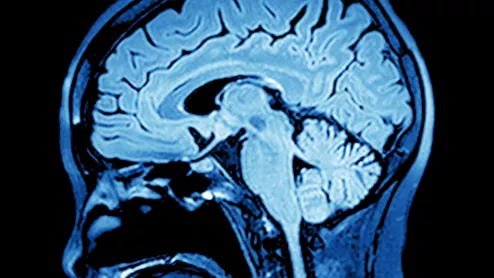

One of the medical specialties highly hopeful in AI’s potential to guide care is neurosurgery. That’s because patients with traumatic brain injuries often present care teams and family members with an especially thorny decision.